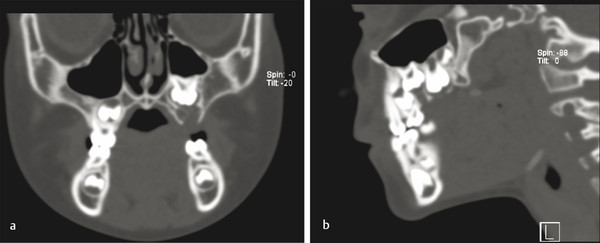

9.4.6 Ameloblastic Fibro-odontoma

Ameloblastic fibro-odontoma (AFO) is usually seen in teenagers as an asymptomatic jaw expansion that may resorb adjacent teeth. It has a mixed radiolucent–radiopaque presentation and is radiographically similar to a developing odontoma (Fig. 9‑9a). Majority of these tumors are found in the posterior mandible and are often associated with an unerupted tooth. Treatment includes simple enucleation and curettage (Fig. 9‑9b, c). Prognosis is excellent, and recurrence is rare.